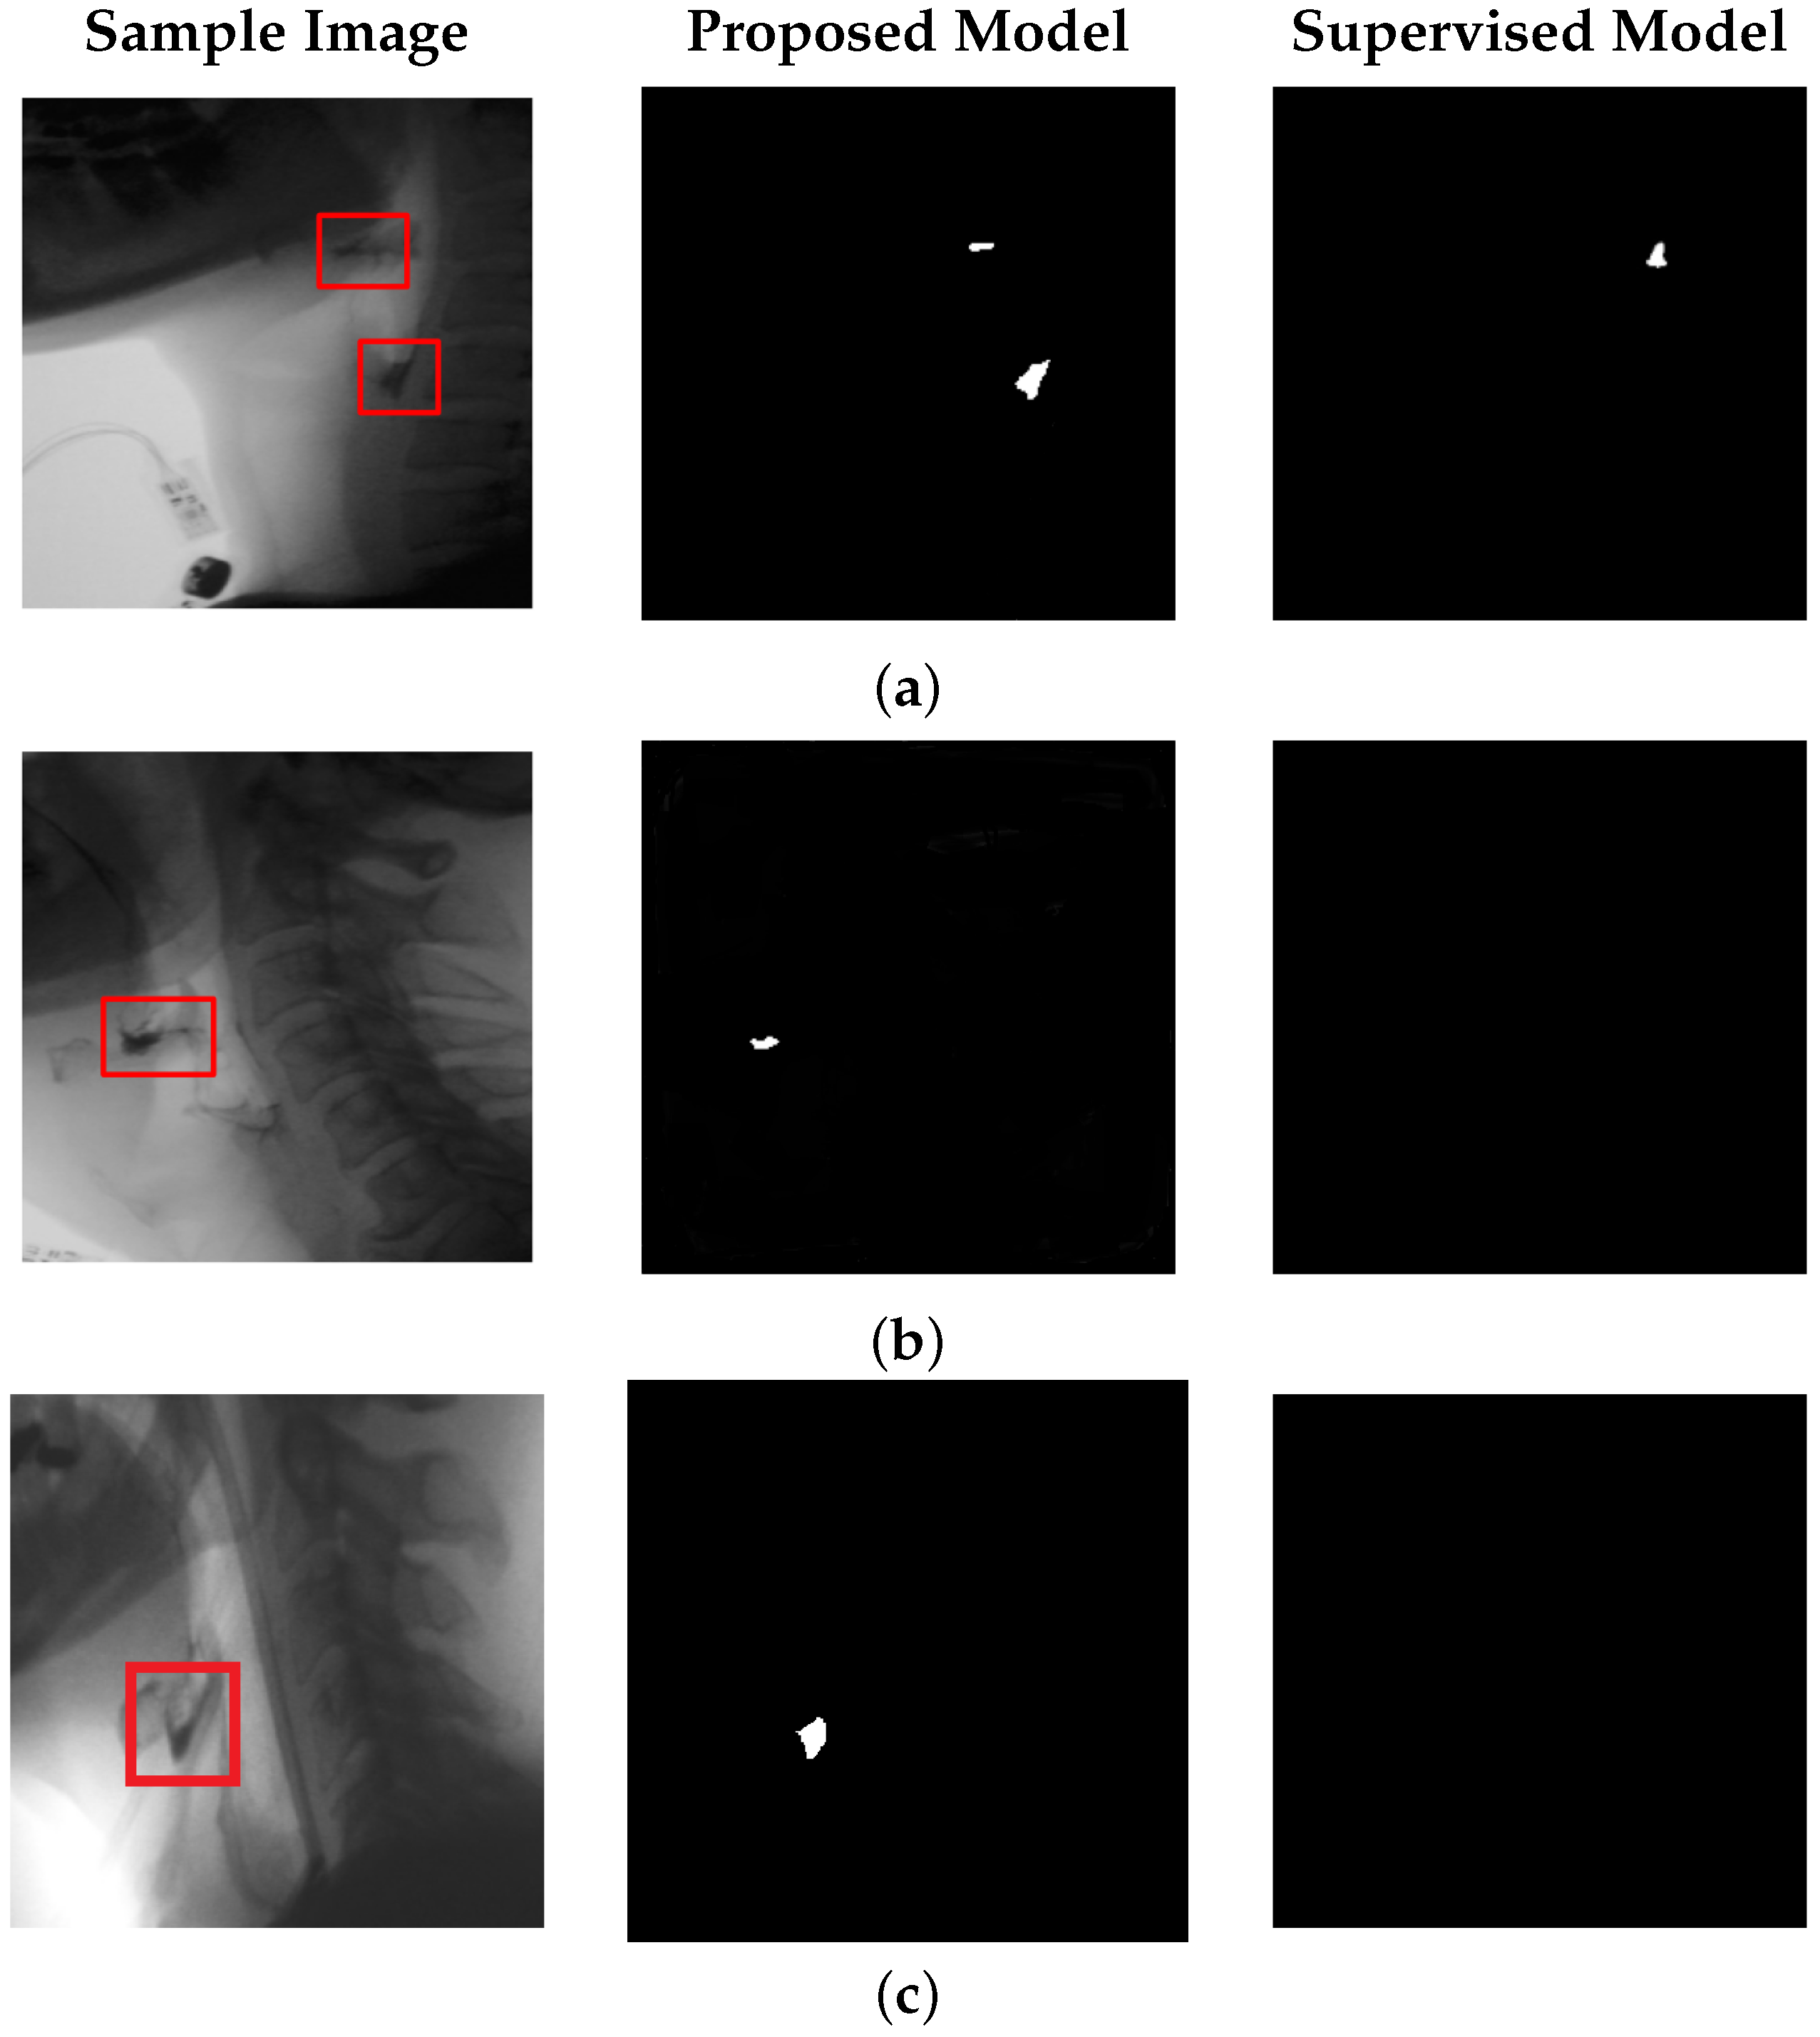

Figure 5 focuses on bolus residue segmentation, showcasing output masks generated by our unsupervised model. The last column also includes results from the supervised model [14] applied to the residue detection task. Although supervised models perform well in bolus tracking, they often struggle with residue detection. These models are typically trained on frames containing well-defined bolus structures, making them less effective at identifying residue, which tends to be smaller, lower in contrast, and more spatially dispersed. As a result, supervised models often fail to generalize, overfitting to the visual characteristics of the bolus and missing the subtle, irregular appearance of residue regions.

In contrast, our unsupervised approach does not rely on explicit object annotations. It learns inherent structural patterns from the data itself, without being constrained by predefined labels. This allows the model to remain sensitive to anomalies—enabling detection of both bolus and bolus residue—while maintaining robustness to normal anatomical variability observed during the swallowing process. Statistical testing confirms that, for residue detection, our method significantly outperforms the state-of-the-art supervised baseline in IoU and DSC metrics ( p < 0.05 , paired t-test; results for the supervised model are detailed in the next subsection).

Figure 5. Performance of the proposed model with positional encoding for bolus residue segmentation. Each row shows a sample test frame, the corresponding residue segmentation produced by our model, and the output from the supervised model [14]. (a) illustrates a case with discontinuous bolus residue, while (b,c) depict frames containing a single residue region.